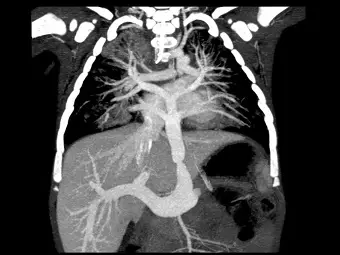

先天性心臟病患者,胸部 CT angiography 顯示全肺靜脈迴流異常( total anomalous pulmonary venous return,TAPVR)如下圖所示。此影像是用何種後處理技術?

- 影像特徵:這是一張冠狀面(Coronal view)的胸腹部電腦斷層血管攝影(CT angiography, CTA)影像。

- 解剖與病理發現:影像中可以清楚看到對比劑充盈的血管樹,以及兩側的肺部血管。仔細觀察解剖異常處,可發現患者的肺靜脈並未正常匯入左心房,而是共同匯聚成一條垂直靜脈(vertical vein),並向下穿過橫膈膜,連接至肝臟的門靜脈系統(portal venous system)。這在臨床上是典型的下心型全肺靜脈迴流異常(Infracardiac TAPVR, Type III)。

- 後處理技術特徵:影像中高密度的構造(施打對比劑的血管與骨骼,如脊椎和肋骨)被特別突顯出來,而背景(如充滿空氣的低密度肺部組織)則顯得暗淡。這種「保留視線穿透路徑上最大 CT 值(Hounsfield Unit)」的視覺效果,使得血管具有前後重疊的透視感與高對比,正是典型的最大強度投影(MIP)。